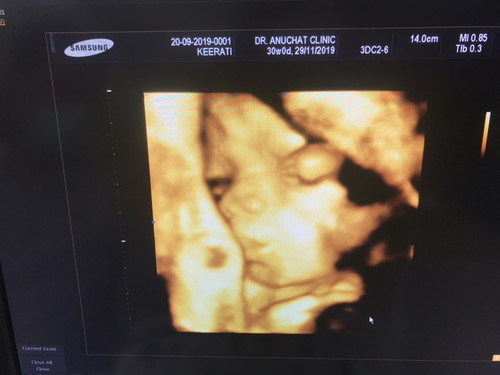

น้องจัสมิน 30 วีค 4D

วันนี้ไปอุลตร้าซาวด์ 4D มาค่ะ ลูกขาชี้ฟ้าบังหน้า กว่าจะเปิดหน้าให้แม่เห็นนี่หมอกระตุ้นจนแม่จุก...เข้าห้องตรวจตอน 12.00 น พยายามทุกวิถีทางให้เห็นหน้าลูกคุณหมอก็ช่วย ผ่านไป 40 นาที ภาพที่ได้นี้ชัดที่สุดแล้วค่ะ??? กำหนดคลอด 29 พย นี้ค่ะ....ตอนนี้แม่ก็กังวลนิดนึงเพราะวางแผลนว่าจะไปคลอดบ้านแฟนที่ต่างประเทศนะคะ วีซ่าก็ยังไม่ออก รอลุ้นว่าจะแตกที่ไทยไหม ??